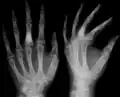

The disease consists of the growth multiple enchondromas which usually develop in early childhood. The growth of these enchondromas usually stops after skeletal maturation.[4] The affected extremity is shortened (asymmetric dwarfism) and sometimes bowed due to epiphyseal fusion anomalies. Bone lesions generally present as cellular during childhood and become more solitary over time. People with Ollier disease are prone to breaking bones (fractures) and normally have swollen, aching limbs. However, many cases of solitary enchondromata go unnoticed due to lack of symptoms. Enchondromas are commonly found in the phalanges, metacarpal, and metatarsal bones in patients of Ollier disease due to the affinity of enchondromas to long tubular bones such as the femur and humerus. A unilateral distribution of bone lesions is usually observed but bilateral distributions or a singular extremity can occur as well. Approximately a third of the cases show some form of physical deformities of bowing or abnormal limb lengthening.

X-ray showing calcified enchondromas localized in finger a 37-year-old patient affected with Ollier disease -